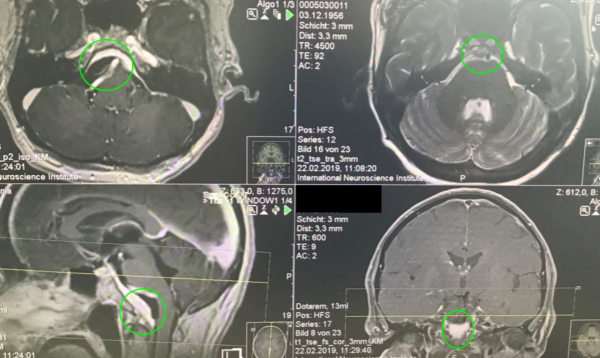

術(shù)前MR示:巖斜區(qū)較大腦膜瘤,壓迫腦干、顱神經(jīng),侵犯基底動脈等

術(shù)后MR顯示:腫瘤近全切除,術(shù)后未見腦血腫、腦水腫,神經(jīng)血管、腦干等組織保護完好